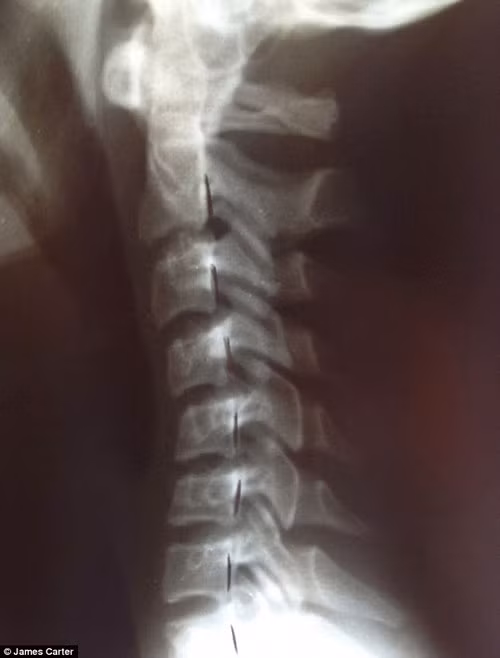

Các phim chụp X-quang cho thấy thanh thiếu niên và trẻ em từ 7 tuổi trở lên, đang ở độ tuổi phát triển nhưng các đốt sống cổ và đốt sống lưng bị cong một cách bất thương. Thậm chí ở một số trẻ còn xuất hiện gai đốt sống, một tình trạng thoái hóa đốt sống thường gặp ở người trung niên.

Phim chụp X-quang cho thấy xương sống của một thiếu nữ 16 tuổi bị vẹo, không chỉ gây mất thẩm mỹ về hình thể mà còn ảnh hưởng đến sức khỏe sau này.

Tiến sỹ Carter nói: "Thay vì xương cổ cong về phía trước như bình thường, cổ của các bệnh nhân cong về phía sau. Nó có thể dẫn đến thoái hóa, thường gây ra đau đầu, cổ, vai và lưng. Nhiều bệnh nhân đến phàn nàn họ thường xuyên đau đầu, nhưng chúng tôi thực sự tìm thấy thoái hóa đốt sống cổ mới là nguyên nhân chính.”